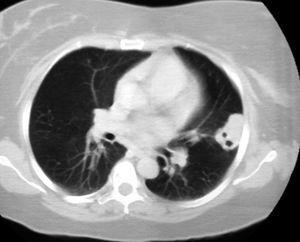

Se presenta el caso de una paciente de 49 años de edad, con antecedentes personales de miomas uterinos, plastia mamaria bilateral 4 años antes y ex fumadora de 15 cigarrillos-día desde hacía 6 meses, que ingresó porque en el estudio preoperatorio para miomectomía uterina se había descubierto en la radiografía de tórax un nódulo pulmonar solitario de 2 cm de diámetro. La paciente se encontraba asintomática desde el punto de vista respiratorio y en la exploración física no se evidenciaron hallazgos patológicos. Las pruebas analíticas no mostraron alteraciones y en la radiografía de tórax destacó la existencia del nódulo pulmonar ya reseñado, de posible asiento en la língula. En la tomografía computarizada se objetivó que dicho nódulo pulmonar medía aproximadamente 2 cm de diámetro, se encontraba cavitado y en íntimo contacto con la pared torácica (fig. 1). La fibrobroncoscopia efectuada fue normal y los resultados obtenidos en dicha exploración no evidenciaron malignidad. Posteriormente se llevó a cabo una punción aspirativa con aguja fina guiada por tomografía computarizada, cuyo resultado fue también negativo para citología y microbiología. Las pruebas funcionales respiratorias, así como la gasometría arterial, fueron normales. Se decidió realizar una toracotomía posterolateral izquierda con resección del segmento afectado. La anatomía patológica de la lesión demostró que se trataba de una GB con intenso componente linfoide y eosinofílico, sin vasculitis apreciable; se realizaron varios tipos de tinciones (Zielh, ácido paraaminosalicílico, plata metanamina), así como diversas técnicas de inmunohistoquímica, sin encontrarse hallazgos relevantes en ellas.

Fig. 1. Nódulo pulmonar subpleural en el lóbulo superior izquierdo, con aparentes imágenes de cavitación en su interior.

La GB, aunque infrecuente, se incluye dentro del posible diagnóstico diferencial del nódulo pulmonar solitario. La presencia de cavitación6, como demuestra el caso que exponemos, no excluye dicho diagnóstico, aunque la primera sospecha diagnóstica debe ser las enfermedades infecciosas o tumorales.